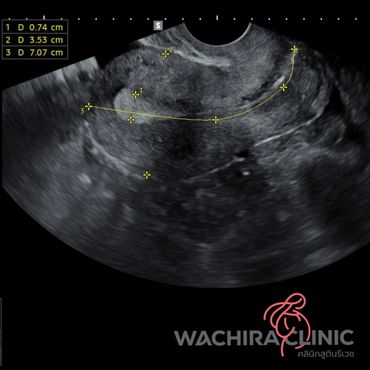

การอัลตราซาวด์มดลูกรังไข่ สามารถบอกความผิดปกติภายในมดลูกและรังไข่ได้ โดยแพทย์จะทำการอัลตราซาวด์ผ่านทางช่องคลอด ซึ่งจะสามารถมองเห็นมดลูกและรังไข่ได้ชัดเจนกว่าการอัลตราซาวด์ผ่านทางหน้าท้อง